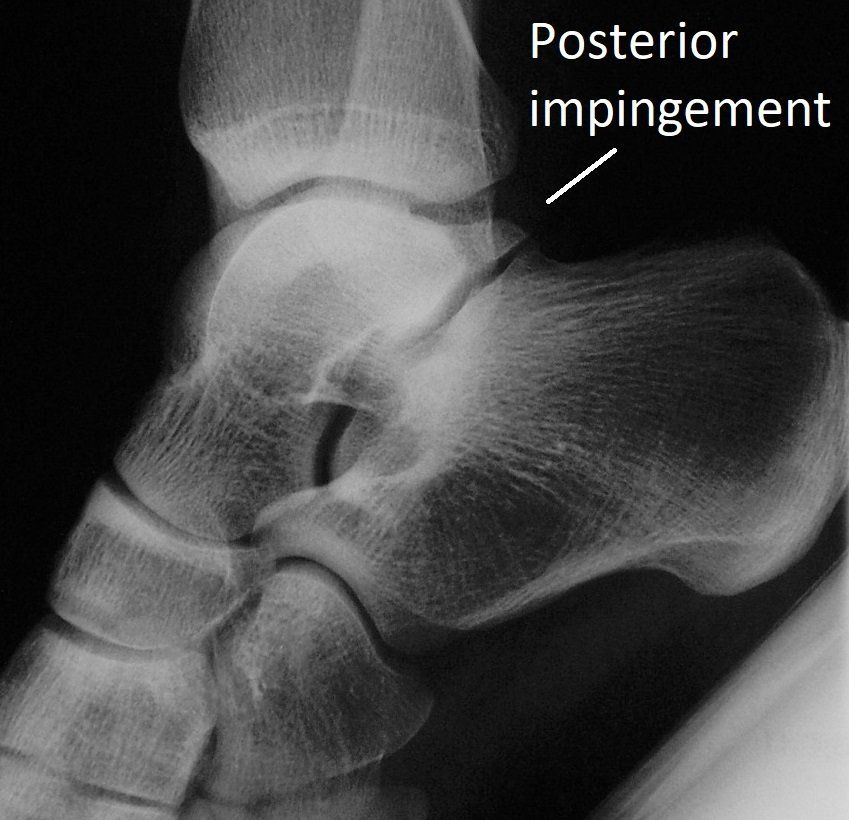

Posterior ankle impingement

is more common in people:

- standing on tip-toes - ballet dancers and football rucks

- landing with the foot bent down - cricket fast bowlers.

This plantar-flexed position

can pinch soft tissue at the back of the ankle (see images below).

- 5% of people are born with an extra bone at the back of the ankle called an os trigonum. This makes posterior impingement more likely.

These investigations determine if the impingement is due to bone spurs, loose bone fragments, arthritis or just soft tissue scarring.